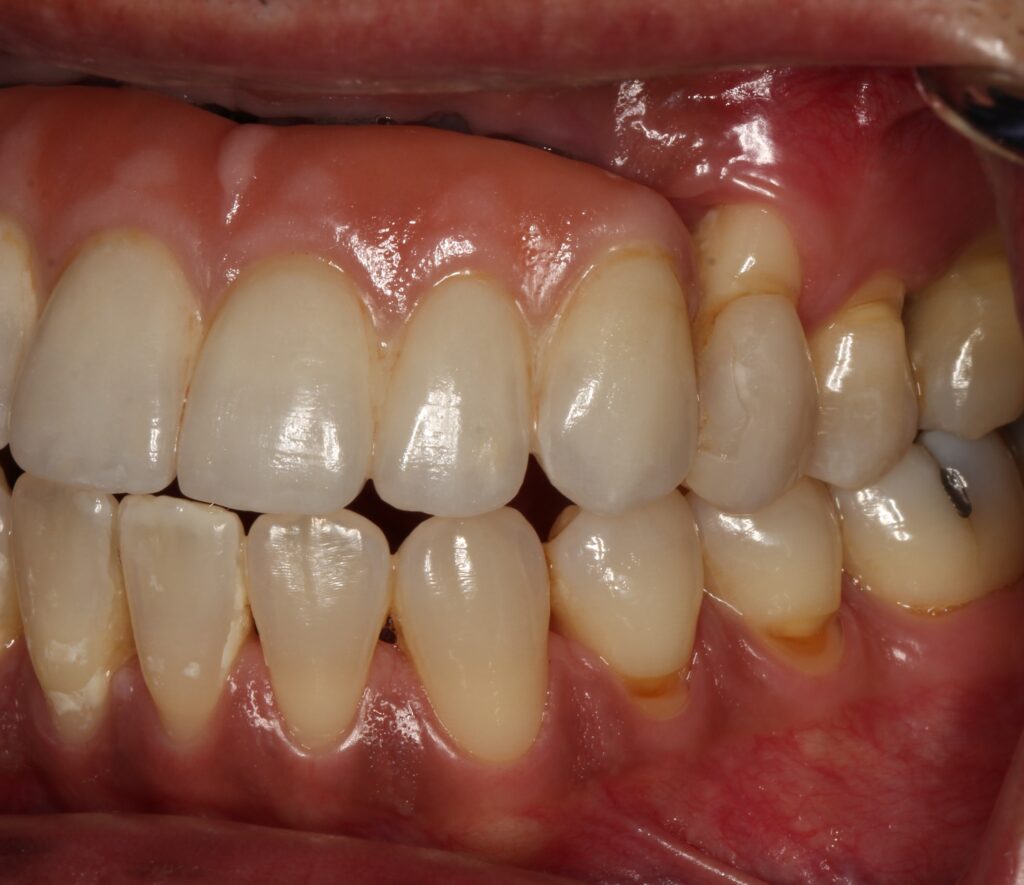

A selection of partial arch fixed implant bridge patients